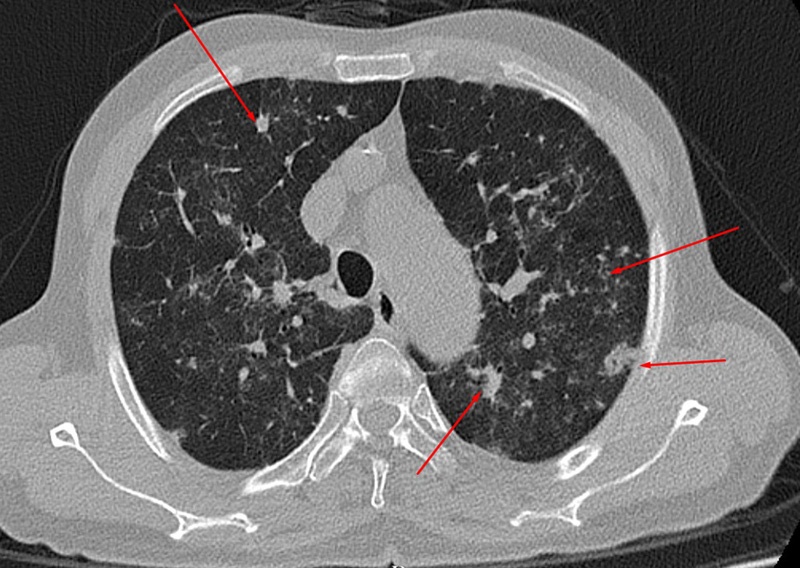

Để xác định tổn thương phổi hậu Covid-19, các bác sĩ sẽ thăm khám lâm sàng, đo chức năng hô hấp, chụp cắt lớp vi tính. Trong đó, chụp cắt lớp vi tính là một trong các phương tiện chẩn đoán hình ảnh được sử dụng nhiều nhất để đánh giá tổn thương phổi với độ chính xác cao.

Chúng cũng có ưu điểm hơn chụp X-quang thường quy do có thể đánh giá được hình thái tổn thương (kính mờ, đông đặc, dải mờ xơ hóa…), vị trí phổi bị tổn thương (bên phải, bên trái, phần trên, phần dưới, ngoại vi, trung tâm), ước lượng thể tích phổi bị tổn thương. Từ đó, bác sĩ có thể tiên lượng cho người bệnh.